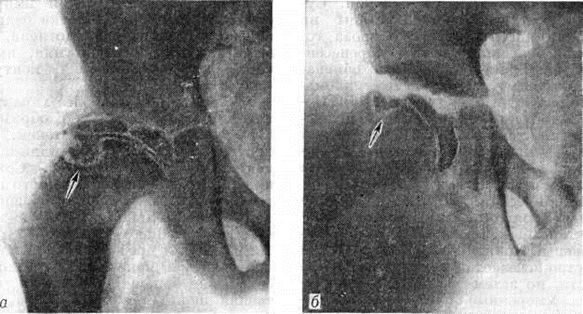

Пертеса болезньПертеса болезнь (G. G. Perthes, немецкий хирург, 1869—1927; синонимы болезнь Легга — Кальве — Пертеса) — асептический некроз головки бедренной кости. Впервые описана Г. Пертесом в 1910 год Пертеса болезнь относится к группе остеохондропатий (смотри полный свод знаний). Составляет 1—3% среди заболеваний опорно-двигательного аппарата у детей. В возрасте до 5 лет встречается редко, наиболее поражаемый возраст 6—10 лет. Мальчики болеют в 4—5 раз чаще. Заболевание обычно носит односторонний характер. Этиология остаётся неясной. Существуют различные взгляды на причину асептического некроза головки бедренной кости (перенесённая инфекция, нарушения обмена, эндокринные расстройства, аномалия развития сосудов, травма). Непосредственной причиной асептического некроза головки бедра следует считать нарушение местного кровообращения, в котором определённую роль может играть травма. Клиническая картина. Первые клинические, симптомы заболевания нехарактерны, непостоянны, слабо выражены. Появляется хромота, которая быстро исчезает при разгрузке конечности, но затем вновь возобновляется. Умеренные боли в области поражённого тазобедренного сустава нередко иррадиируют в коленный сустав. Боли обычно возникают днём, во время ходьбы. Клинические, исследование выявляет незначительную атрофию мягких тканей бедра и голени, небольшую сгибательную контрактуру тазобедренного сустава, ограничение отведения и внутренней ротации бедра. Пальпация тазобедренного сустава слегка болезненна. G разгрузкой сустава (постельный режим) указанные жалобы быстро исчезают. Симптом Александрова (смотри полный свод знаний Туберкулёз внелёгочный, туберкулёз костей и суставов) слабо положительный или отсутствует. Длина конечности, как правило, не изменена, но может наблюдаться небольшое укорочение или удлинение её в связи с угнетением или раздражением росткового хряща. Симптом Тренделенбурга (смотри полный свод знаний Тазобедренный сустав) в большинстве случаев положительный. Общее состояние ребёнка не страдает. Температура не повышена, кровь в норме. Диагностика. В связи с отсутствием характерных клинические, признаков Пертеса болезнь часто диагностируют с опозданием. Решающую роль в диагностике играет рентгенологическое исследование, при этом обязательна рентгенография обоих тазобедренных суставов в прямой проекции и в положении Лауэнштейна (смотри полный свод знаний Тазобедренный сустав). Пертеса болезнь характеризуется определённой последовательностью морфологический изменений, происходящих в головке бедренной кости, что рентгенологически выражается 5 стадиями процесса (С. А. Рейнберг). В первой стадии (стадия подхрящевого некроза) отмечают остеопороз головки и шейки бедра, расширение суставной щели. Головка теряет сферическую форму, под куполом её появляется узкая полоска просветления, что свидетельствует о начальных стадиях сплющивания. Все эти изменения более отчётливо видны на рентгенограмме тазобедренного сустава в положении Лауэн. Вторая стадия — стадия импрессионного перелома: головка бедренной кости уплощена, уплотнена, лишена структурного рисунка, имеет неровные извилистые контуры (рисунок 1). Третья стадия, наиболее характерная для Пертеса болезнь,— стадия с образованием секвестроподобных теней. Некротические массы расщепляются и постепенно рассасываются. Сохранившиеся островки гомогенного некроза, окружённые вновь образованной соединительной тканью и хрящом, напоминают секвестры (рисунок 2, а). Если ребёнок продолжает пользоваться конечностью, головка бедра ещё больше уплощается, суставная щель становится шире, чем во второй стадии. Щель эпифизарного хряща расширяется, приобретает извилистые рыхлые контуры. Шейка утолщается и укорачивается в результате нарушения процессов энхондрального роста. В тяжёлых случаях в субхондральных её отделах выявляются очаги разрежения. Соответственно деформации головки бедра изменяется и форма вертлужной впадины, её крыши. Проксимальный конец бедра может быть смещён в положение небольшого подвывиха кнаружи и кверху. Четвертая стадия — стадия восстановления структуры (рисунок 2, б). Секвестроподобные тени не определяются, но структура головки долгое время остаётся неравномерной, постепенно приобретая нормальный губчатый рисунок. Деформация головки сохраняется на всю жизнь. Чётких рентгенологических границ между описанными четырьмя стадиями не существует. |